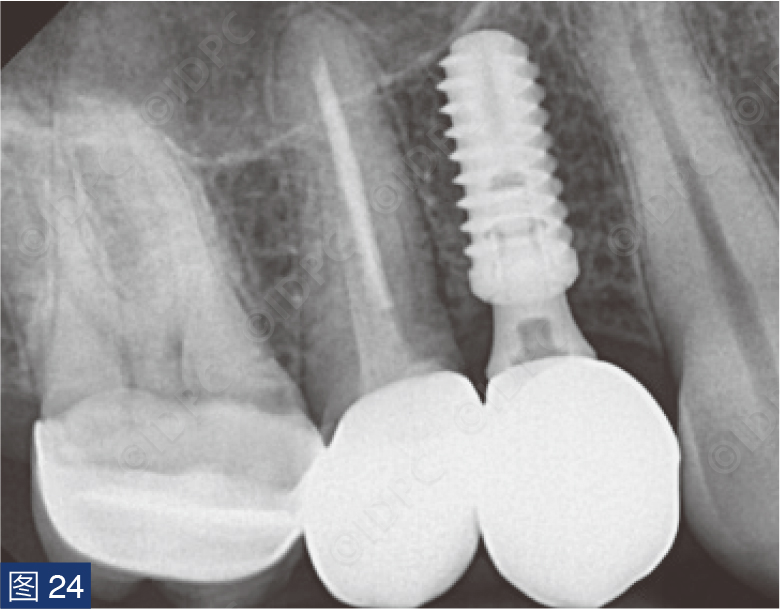

在exocad软件(exocad公司)上进行全数字化修复流程设计,在copaSKY uni.fit钛基底(bredent medical公司)上制作完成螺丝固位氧化锆混合陶瓷一体冠。种植位点显示出足够的颊侧软组织厚度(图12a)及良好的牙龈轮廓(图12b)。取下个性化愈合基台后,种植体周围软组织健康(图13、14),此外,取下后立即进行术前口内扫描以记录软组织轮廓。随后放置扫描体并进行数字印模以记录种植体位置(图15)。同时扫描对颌牙弓及咬合信息。获得的STL文件以数字方式发送至技工室。技工室在钛基底上完成聚甲基丙烯酸甲酯(PMMA)材料的试戴牙冠,以检查邻接和边缘密合情况,同时调整咬合(图16、17)。一旦完成所有调整,进行重新扫描。最终在钛基底上完成螺丝固位的全结构氧化锆混合陶瓷修复体,与牙龈接触的修复体表面高度抛光(图18),并以25 Ncm戴入口内。修复体实现了出色的颜色匹配及临床结果(图19)。螺丝孔用聚四氟乙烯填塞并用树脂材料密封(图20)。术后对照X线片显示修复体正确就位(图21)。六个月复查,增加的软组织轮廓清晰可见,牙槽骨水平保持稳定(图22-24)。

个性化愈合基台通过将树脂材料粘固至钛基底上制成,用于在愈合期间调节软组织形态(图8)。个性化的愈合基台模仿所谓的“郁金香形状”,以创造更理想的穿龈轮廓。使用6-0不可吸收单丝线(Optilene,B. Braun公司)无张力缝合固定软组织(图9a、9b)。术后X线片显示植体与邻牙平行放置(图10)。向患者提供术后指导,以保持植入部位的口腔卫生。